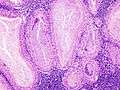

Histopathology of Warthin tumor in the parotid gland. Higher magnification of a file "Warthin tumor (1).jpg". H&E stain.